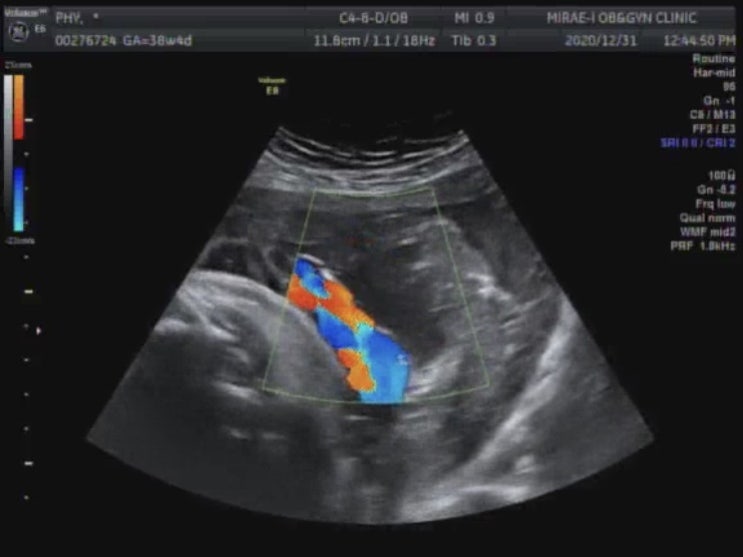

아듀 2020 - 임신 38주4일 -첫내진 - 자연진통 기다리기

#임신38주 #임신10개월 #첫내진 #태아몸무게 #아듀2020 오늘로 임신 38주4일. 저번주 화요일에 검진을 갔으...